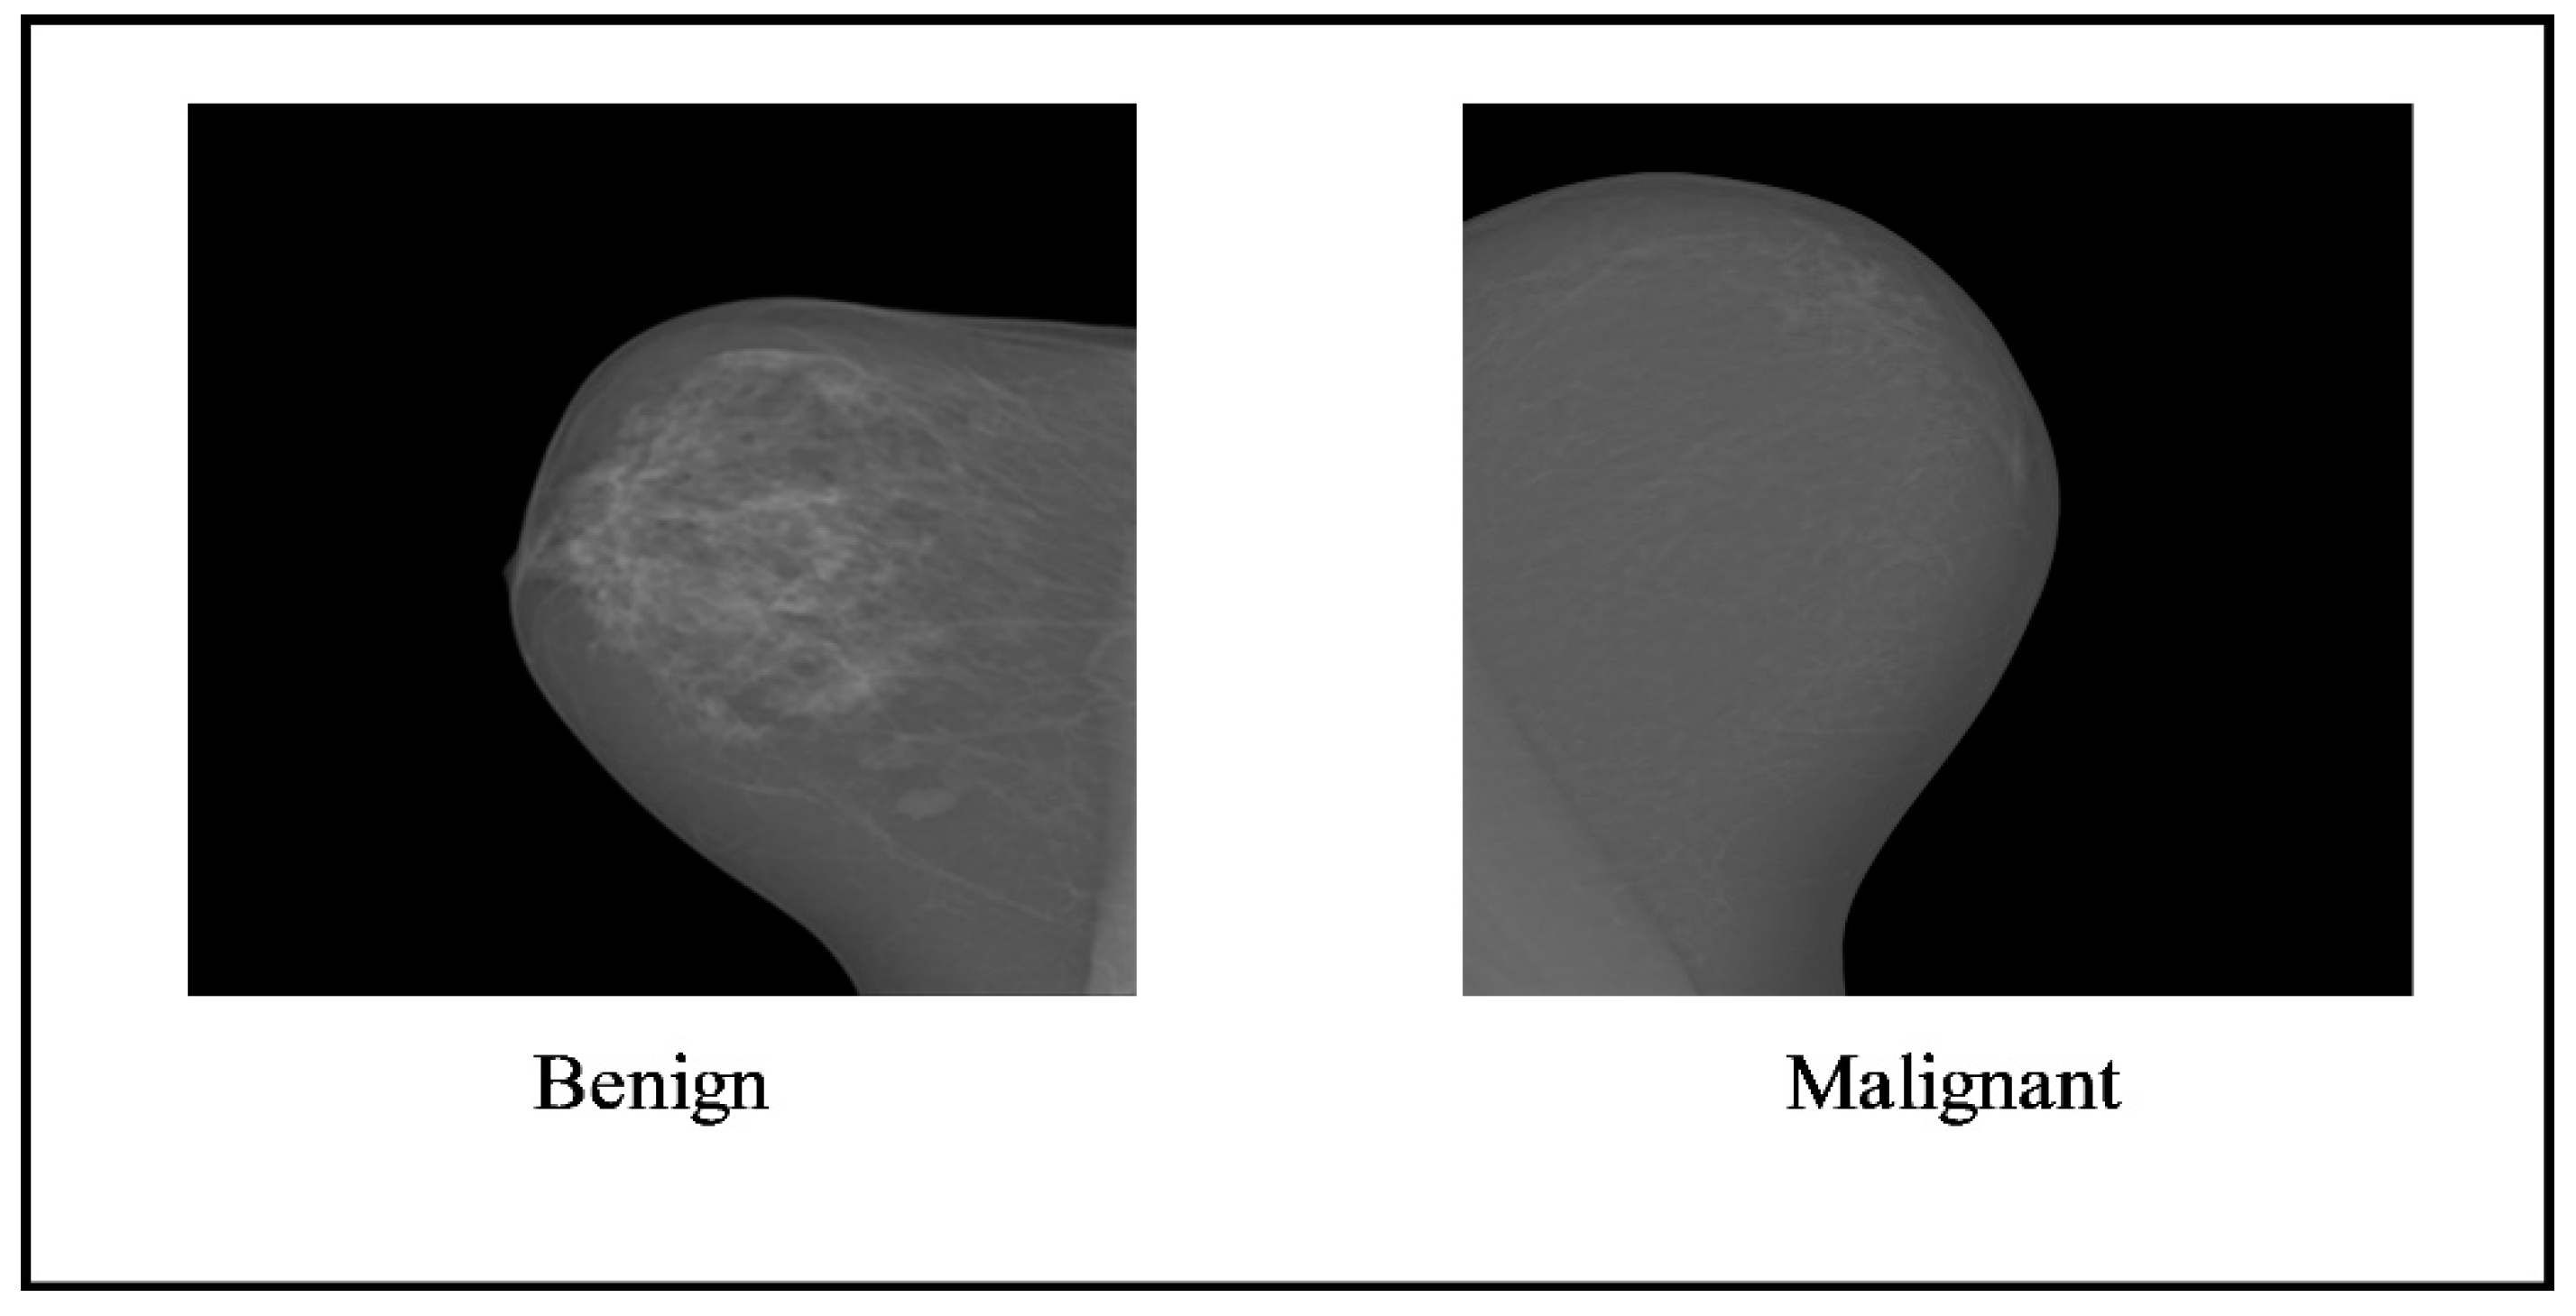

In this section, the details of selected datasets have been presented. Two datasets have been employed for the experimentation of this work, such as the CBIS-DDSM (the Curated Breast Imaging Subset of DDSM), where the digital database is a revised and standardized version of scanning for breast cancer (DDSM) and INbreast. The DDSM dataset comprises two classes, benign and malignant, as shown in Figure 2.

Figure 2. Sample images of the CBIS-DDSM dataset [38].